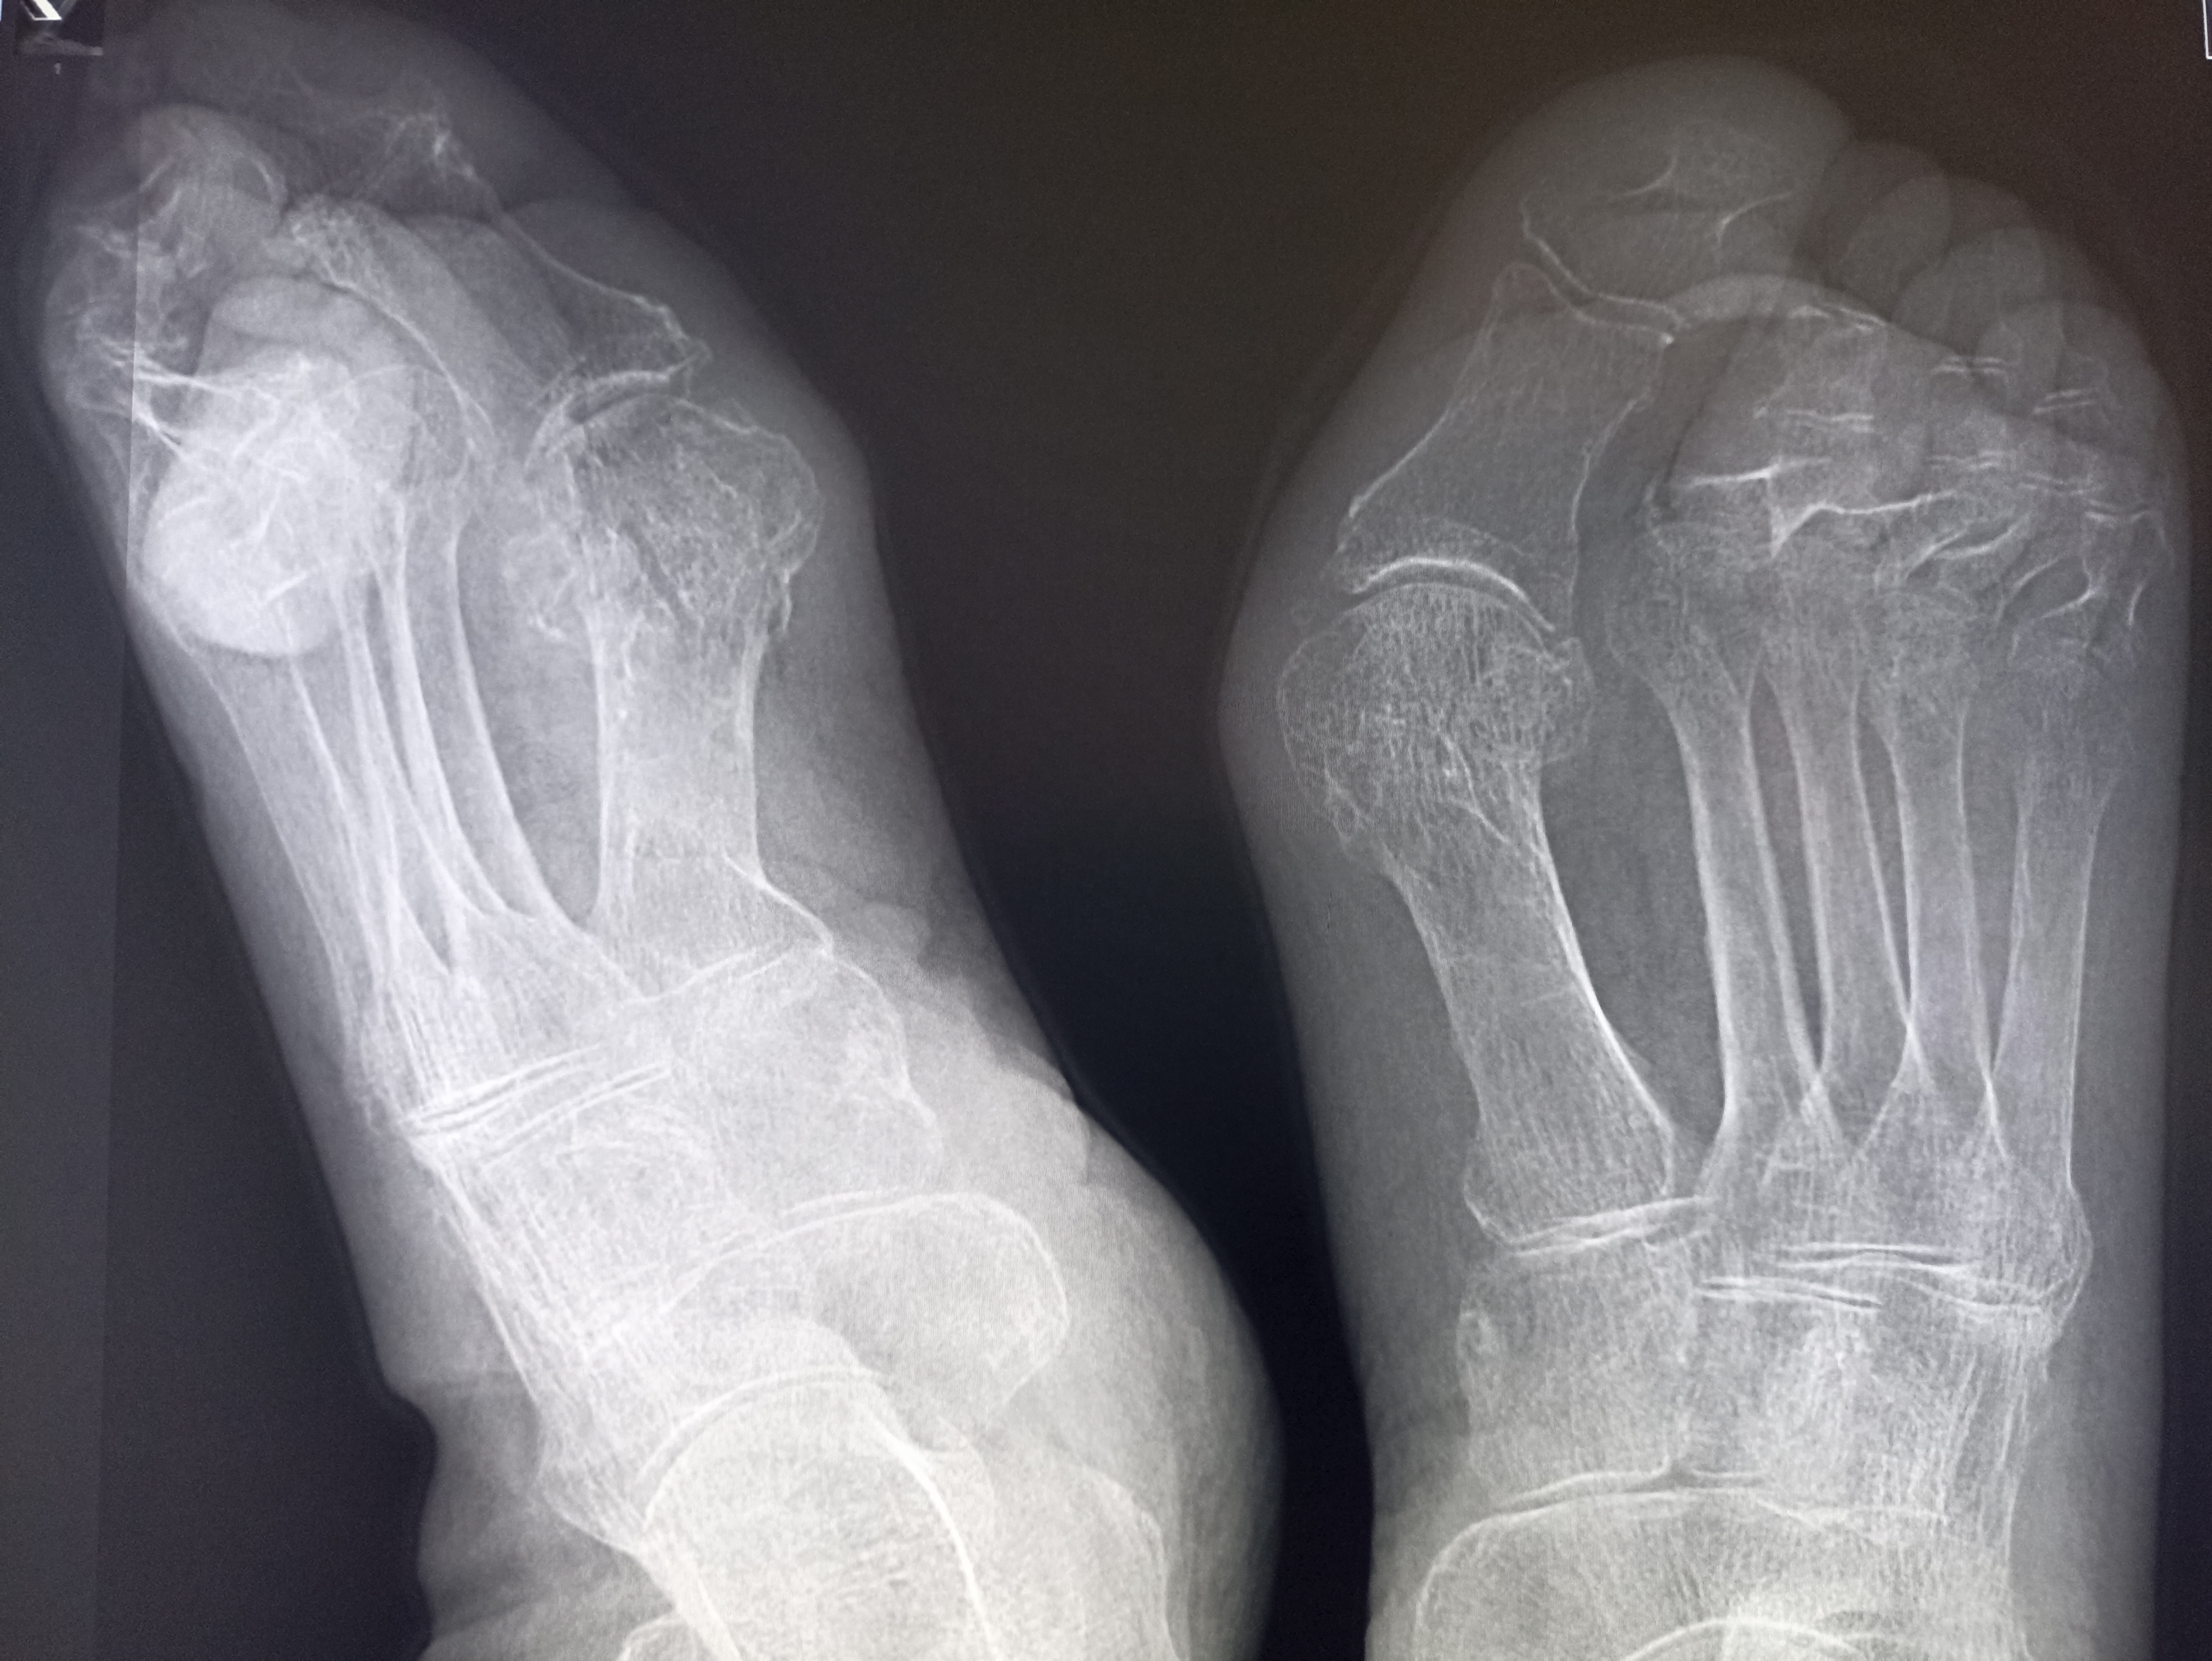

IMG20251014105834.jpg

Чо тут у нас?

>>325599083

Удар об угол дивана?

>>325599234

Ни, прост вальгусная деформация

Плов я вчера доел, в вс приготовил, а от макарошек я с диетической целью отрекся не могу контролировать их поедание :-(

Вальгусная деформация пальцев стопы?

>>325604511

да